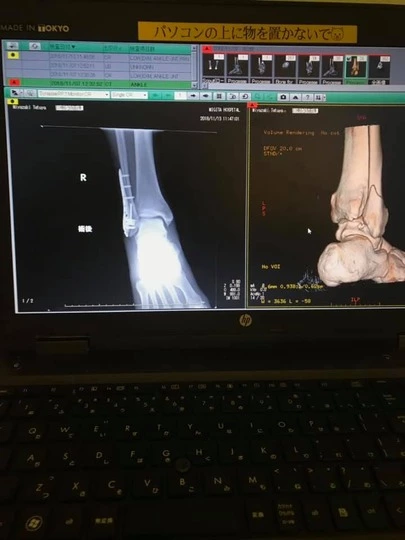

さて、突然ですが、11月5日にそれはそれはたいそう派手に転んでしまい、「右足腓骨遠位端骨折」というものをしました。( ;∀;)

これまでの人生、自分は骨太だから、骨は折れないと真面目に思っていましたが、度が過ぎれば折れる時は折れるんですね。(当たり前ですが…😂)人生初の全身麻酔の手術をし、“金属プレート”を入れました。